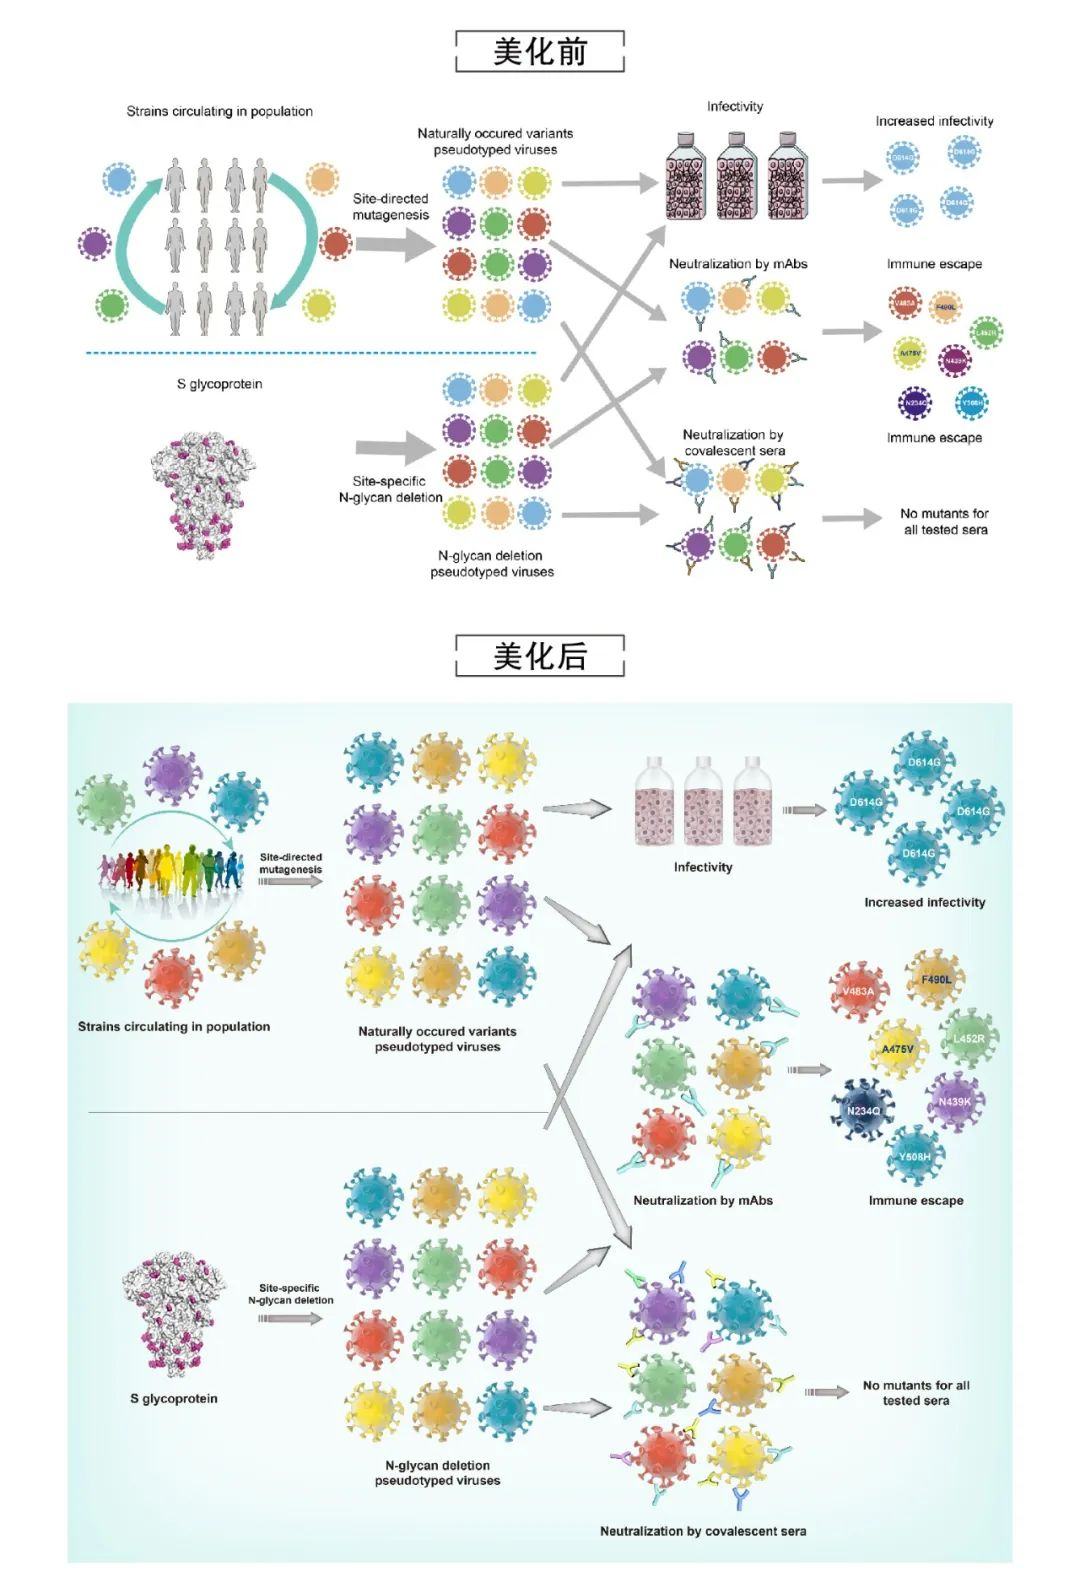

论文图表美化

滑动查看更多 点击查看大图